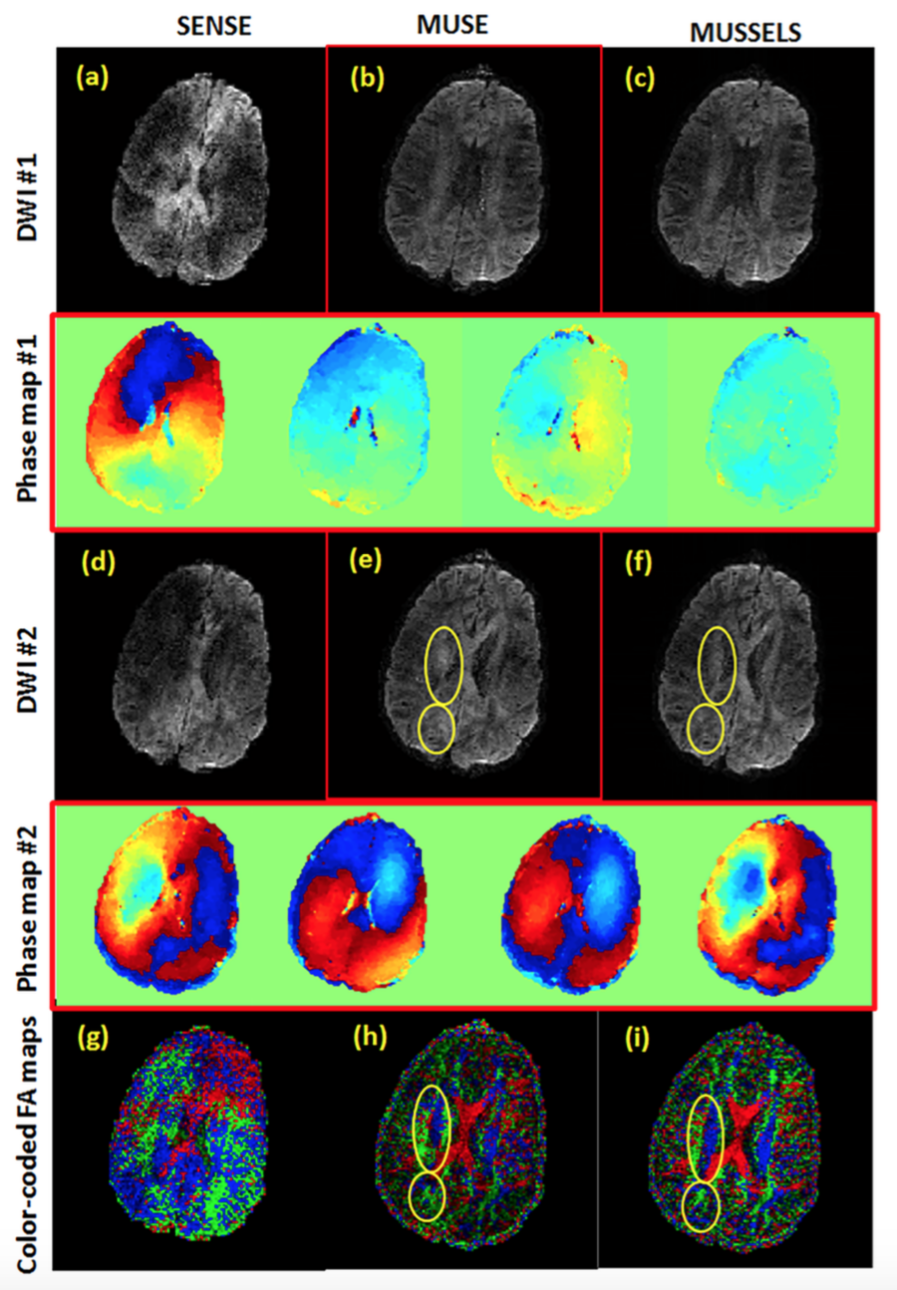

Next we compare the performance of MUSSELS with the standard method that use motion-induced phase estimates to achieve unaliasing of the DWIs. Figure 6 shows two sample DWIs corresponding to two different diffusion directions reconstructed from the 4-shot acquisition using a regular SENSE method, the MUSE method and MUSSELS. As can be seen from the figure, MUSE is successful in unaliasing the first DWI (Fig. 6 DWI ), but not the the second DWI (Fig. 6 DWI ). The phase maps used in the recovery of the DWIs for MUSE reconstruction are also included in the figure. A six direction diffusion scheme was used here to highlight the errors originating from the reconstruction in the computation of the fiber directions. The color coded FA maps given in the last row shows the smearing of fiber orientation in the case of MUSE whereas the fiber orientations are accurately recovered using MUSSELS. Note that the same coil sensitivity maps were used in all the reconstructions.

Fig 6: DWI and DWI are two diffusion weighted images corresponding to two different diffusion directions. The first row shows (a) conventional SENSE, (b) MUSE and (c) MUSSELS reconstruction for DWI . While MUSE and MUSSELS effectively unaliased the ghosting artifacts for DWI , SENSE reconstruction shows residual artifacts. The second row shows the motion-induced phase maps that were estimated as part of MUSE reconstruction for the four shots of the DWI shown in the first row. The third row shows (d) SENSE, (e) MUSE and (f) MUSSELS reconstruction for DWI . In this case, the MUSE reconstruction was not effective in unaliasing the ghosting artifacts. SENSE reconstruction also shows the ghosting whereas MUSSELS shows good unaliasing. The fourth row shows the phase maps used by MUSE for the DWI shown in the third row. The final row shows the color-coded fractional anisotropy maps recovered using SENSE (g), MUSE (h) and MUSSELS (i). A six direction DTI acquisition was used to highlight the errors in tensor estimation due to the residual aliasing present in the six DWIs.